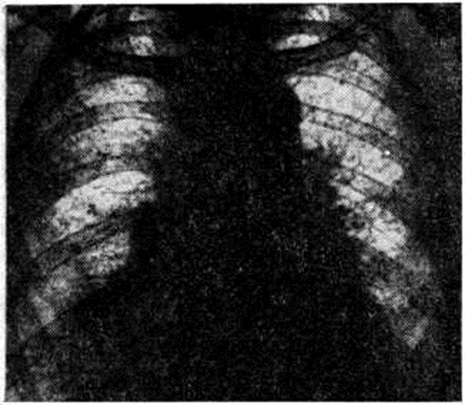

Диагноз устанавливают на основании характерных клинические, признаков. Среди дополнительных методов исследования важным является рентгенологический. Ранними рентгенологическое признаками Хаммена — Рича синдром являются усиление и деформация лёгочного рисунка, обычно выявляемые в нижних и средних отделах лёгочных полей. Прозрачность этих участков понижается за счёт появления множества тяжистых теней, идущих радиально от корней к периферии по ходу бронхов и сосудов. Характерен сетчатый, ячеистый рисунок, обусловленный разрастанием соединительной ткани вокруг долек и ацинусов (рисунок).

По мере прогрессирования процесса обмечается уплотнение теней корней и утолщение пристеночной, междолевой и диафрагмальной плевры; верхние отделы лёгких также постепенно вовлекаются в патологический процесс. На фоне усиленного и деформированного лёгочного рисунка появляются нечётко очерченные очаговые тени небольших и средних размеров, частично сливающиеся между собой. Подвижность диафрагмы уменьшается, реберно-диафрагмальные синусы частично, а затем полностью облитерируются.

При далеко зашедшем процессе в кортикальном слое лёгких по периферии лёгочных полей появляются кистовидные полости, диаметром до 2—3 сантиметров, некоторые с уровнем жидкости. Томография (смотри полный свод знаний) и бронхография (смотри полный свод знаний) позволяют иногда обнаружить цилиндрические, мешотчатые и смешанные бронхоэктазы, обычно в нижнемедиальных отделах лёгких. Характерным для течения Хаммена — Рича синдром является неуклонное нарастание отмеченных рентгенологическое изменений.

Рентгенограмма грудной клетки больного с синдромом Хаммена — Рича (прямая проекция): резкое усиление и тяжисто-ячеистая деформация лёгочного рисунка.